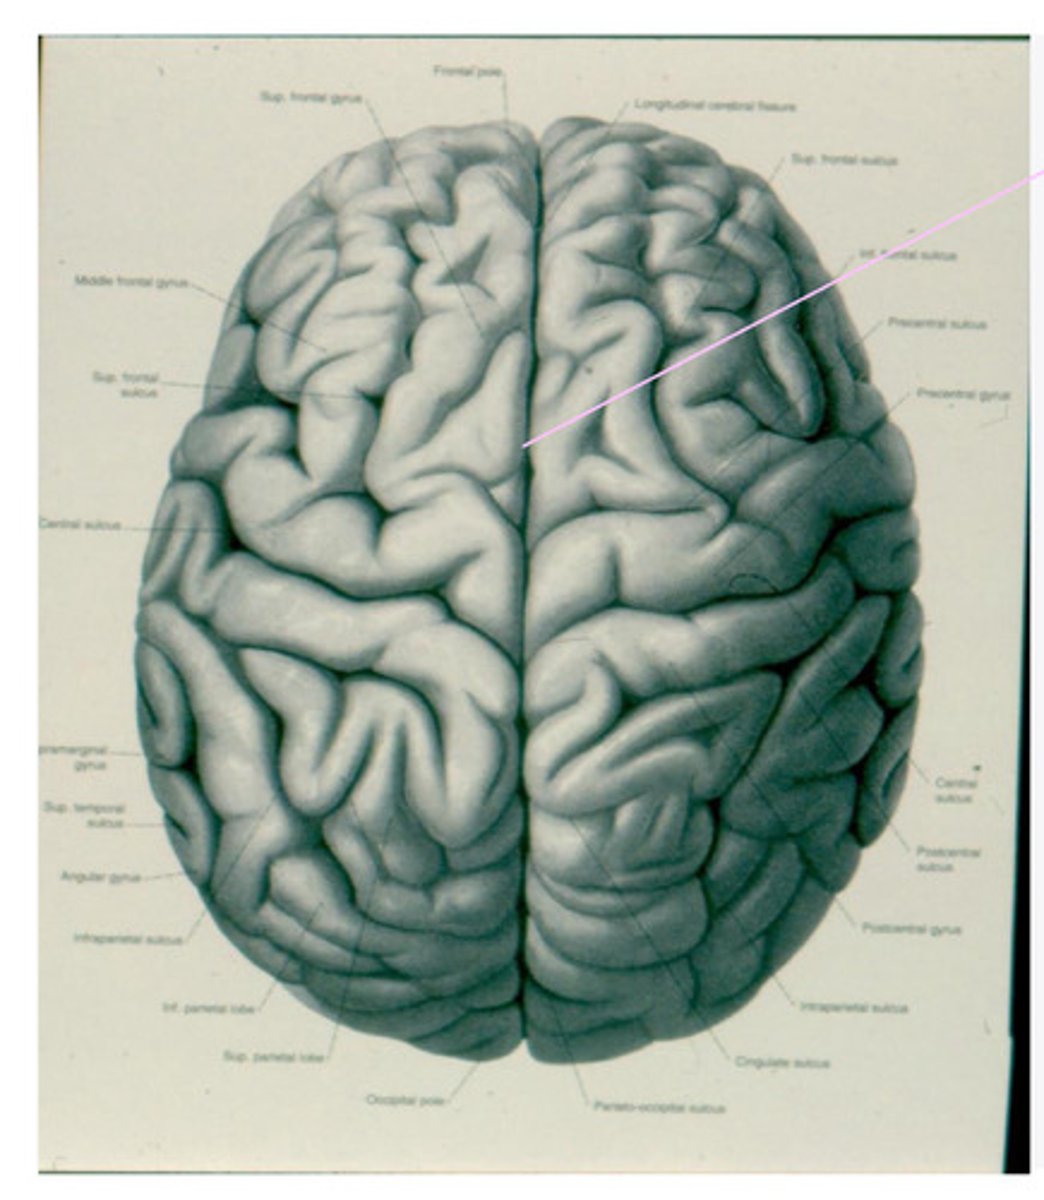

geri, sulci, lobes

What are the anatomical divisions of the cortex of the brain?

-frontal

-parietal

-temporal

-occipital

What are the 4 lobes of the brain?

central sulcus

What sulcus differentiates the frontal from the parietal lobe?

lateral sulcus

-precentral gyrus

-superior frontal gyrus

-middle frontal gyrus

-inferior frontal gyrus

-post-central gyrus

-superior parietal lobule

-inferior parietal lobule

What are the divisions of the parietal lobe?

-supramarginal gyrus

-angular gyrus

What are the divisions of the inferior parietal lobule?